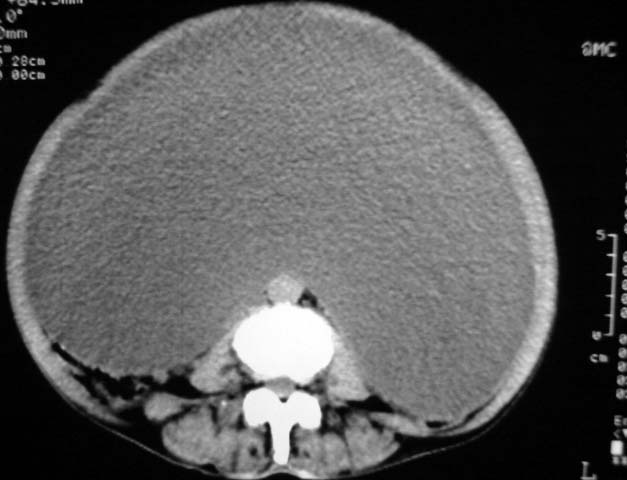

女,75岁,腹部胀大半年余,无其他症状。

考虑来源与卵巢的巨大囊腺瘤或囊肿。

1、考虑卵巢巨大囊腺瘤或囊肿。2、子宫肌瘤不除外。

考虑来源卵巢巨大黏液性囊腺瘤。